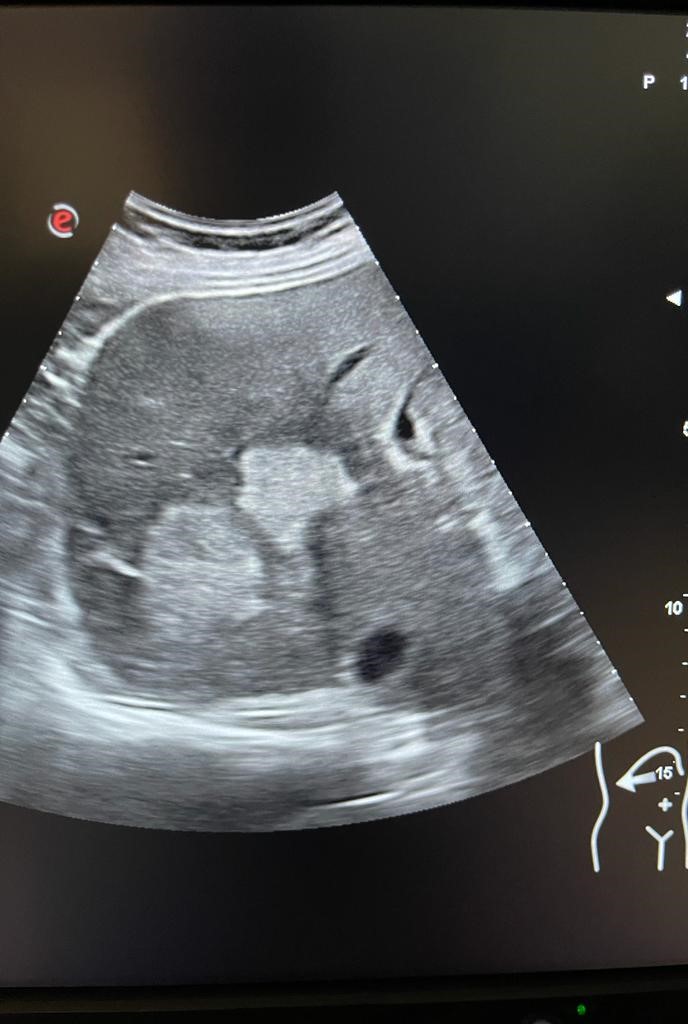

Se aprecia hígado heterogéneo con múltiples LOES hepáticas hiperecogénicas (una de ellas de unos 7x7 cm), sin captación de doppler. Al menos otras 2 LOES de menor tamaño presentan halo hipoecoico. Vesícula replecionada de contornos lisos y sin litiasis en su interior. Ambos riñones visualizados de tamaño normal y sin datos de hidronefrosis.

Se decide pedir ecografía reglada para valorar estudio posterior. Ecografía confirma sospecha de LOES intrahepáticas. Desde radiología amplian estudio con TAC: lesión ósea lítica con criterios de agresividad expansiva con masa de partes blandas en vertiente posterior de pala ilíaca izquierda.